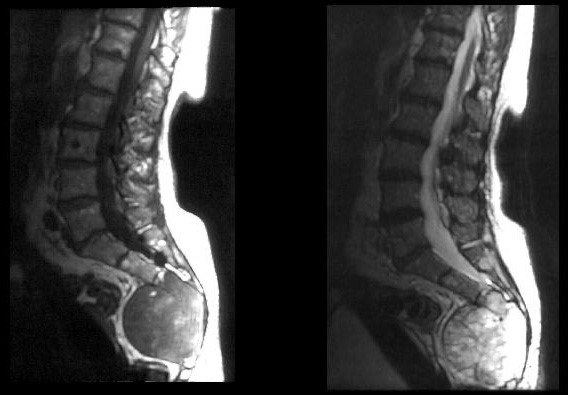

- КТ или МРТ назначаются при подозрении на метастазы;